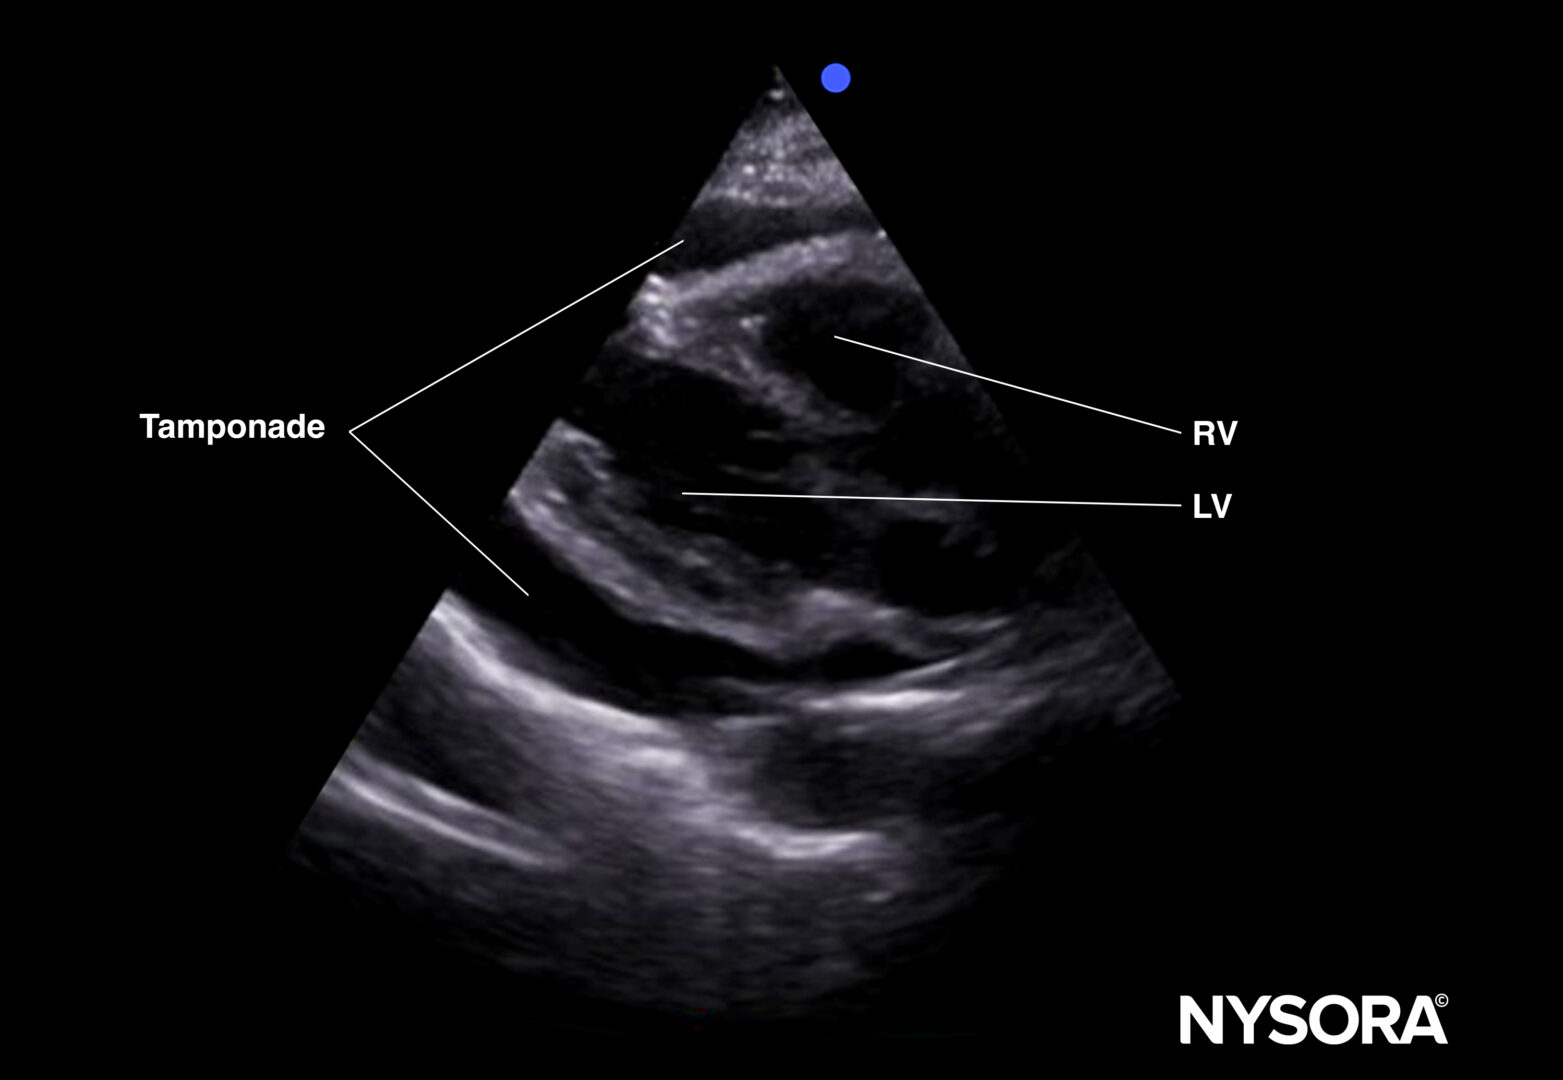

Tamponade:

Fluid can collect in the pericardial space, decreasing cardiac output by interfering with cardiac filling.

Ultrasound features: Anechogenic layer between the heart and the pericardium.

Tamponade (parasternal long-axis view).

Tamponade (parasternal short-axis view).